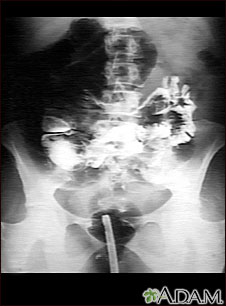

Serie GI en un paciente con torsión intestinal (vólvulo).